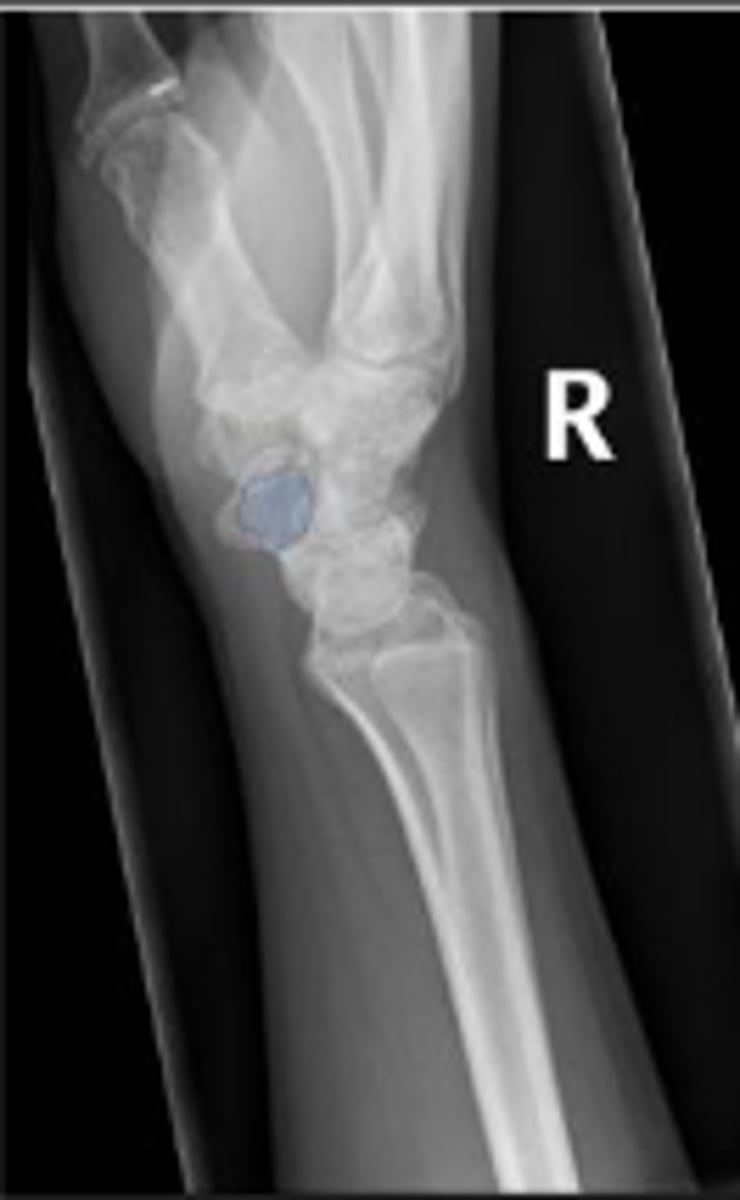

Left lateral wrist

What is the name of the radiographic view?

Right trapezoid

What is outlined?

Right capitate

Right lunate

Right hamate